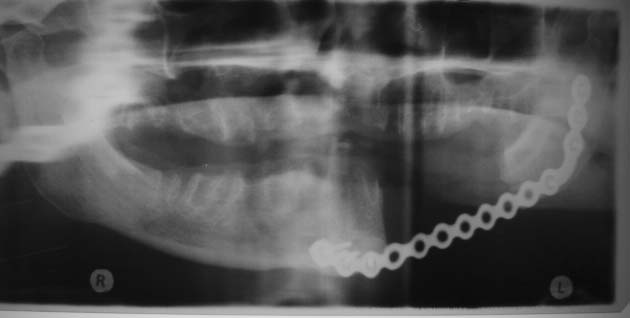

Head and Neck Tumor and Reconstruction

(cancer reconstruction)

Often after a patient has gone through various treatments for cancer there is a need that oral and maxillofacial services can provide for. In many cases, reconstructive surgery benefits patients having gone through specific skin cancers that are typically found in and around the head and neck regions. Depending on the severity and location of the cancer, skin cancer reconstruction options can range from simple to advanced procedures in order to restore both function and form.

The photos on this website are from real surgeries performed by Dr. Ulloa. Due to the

graphic nature of the images and content, viewer discretion is advised.